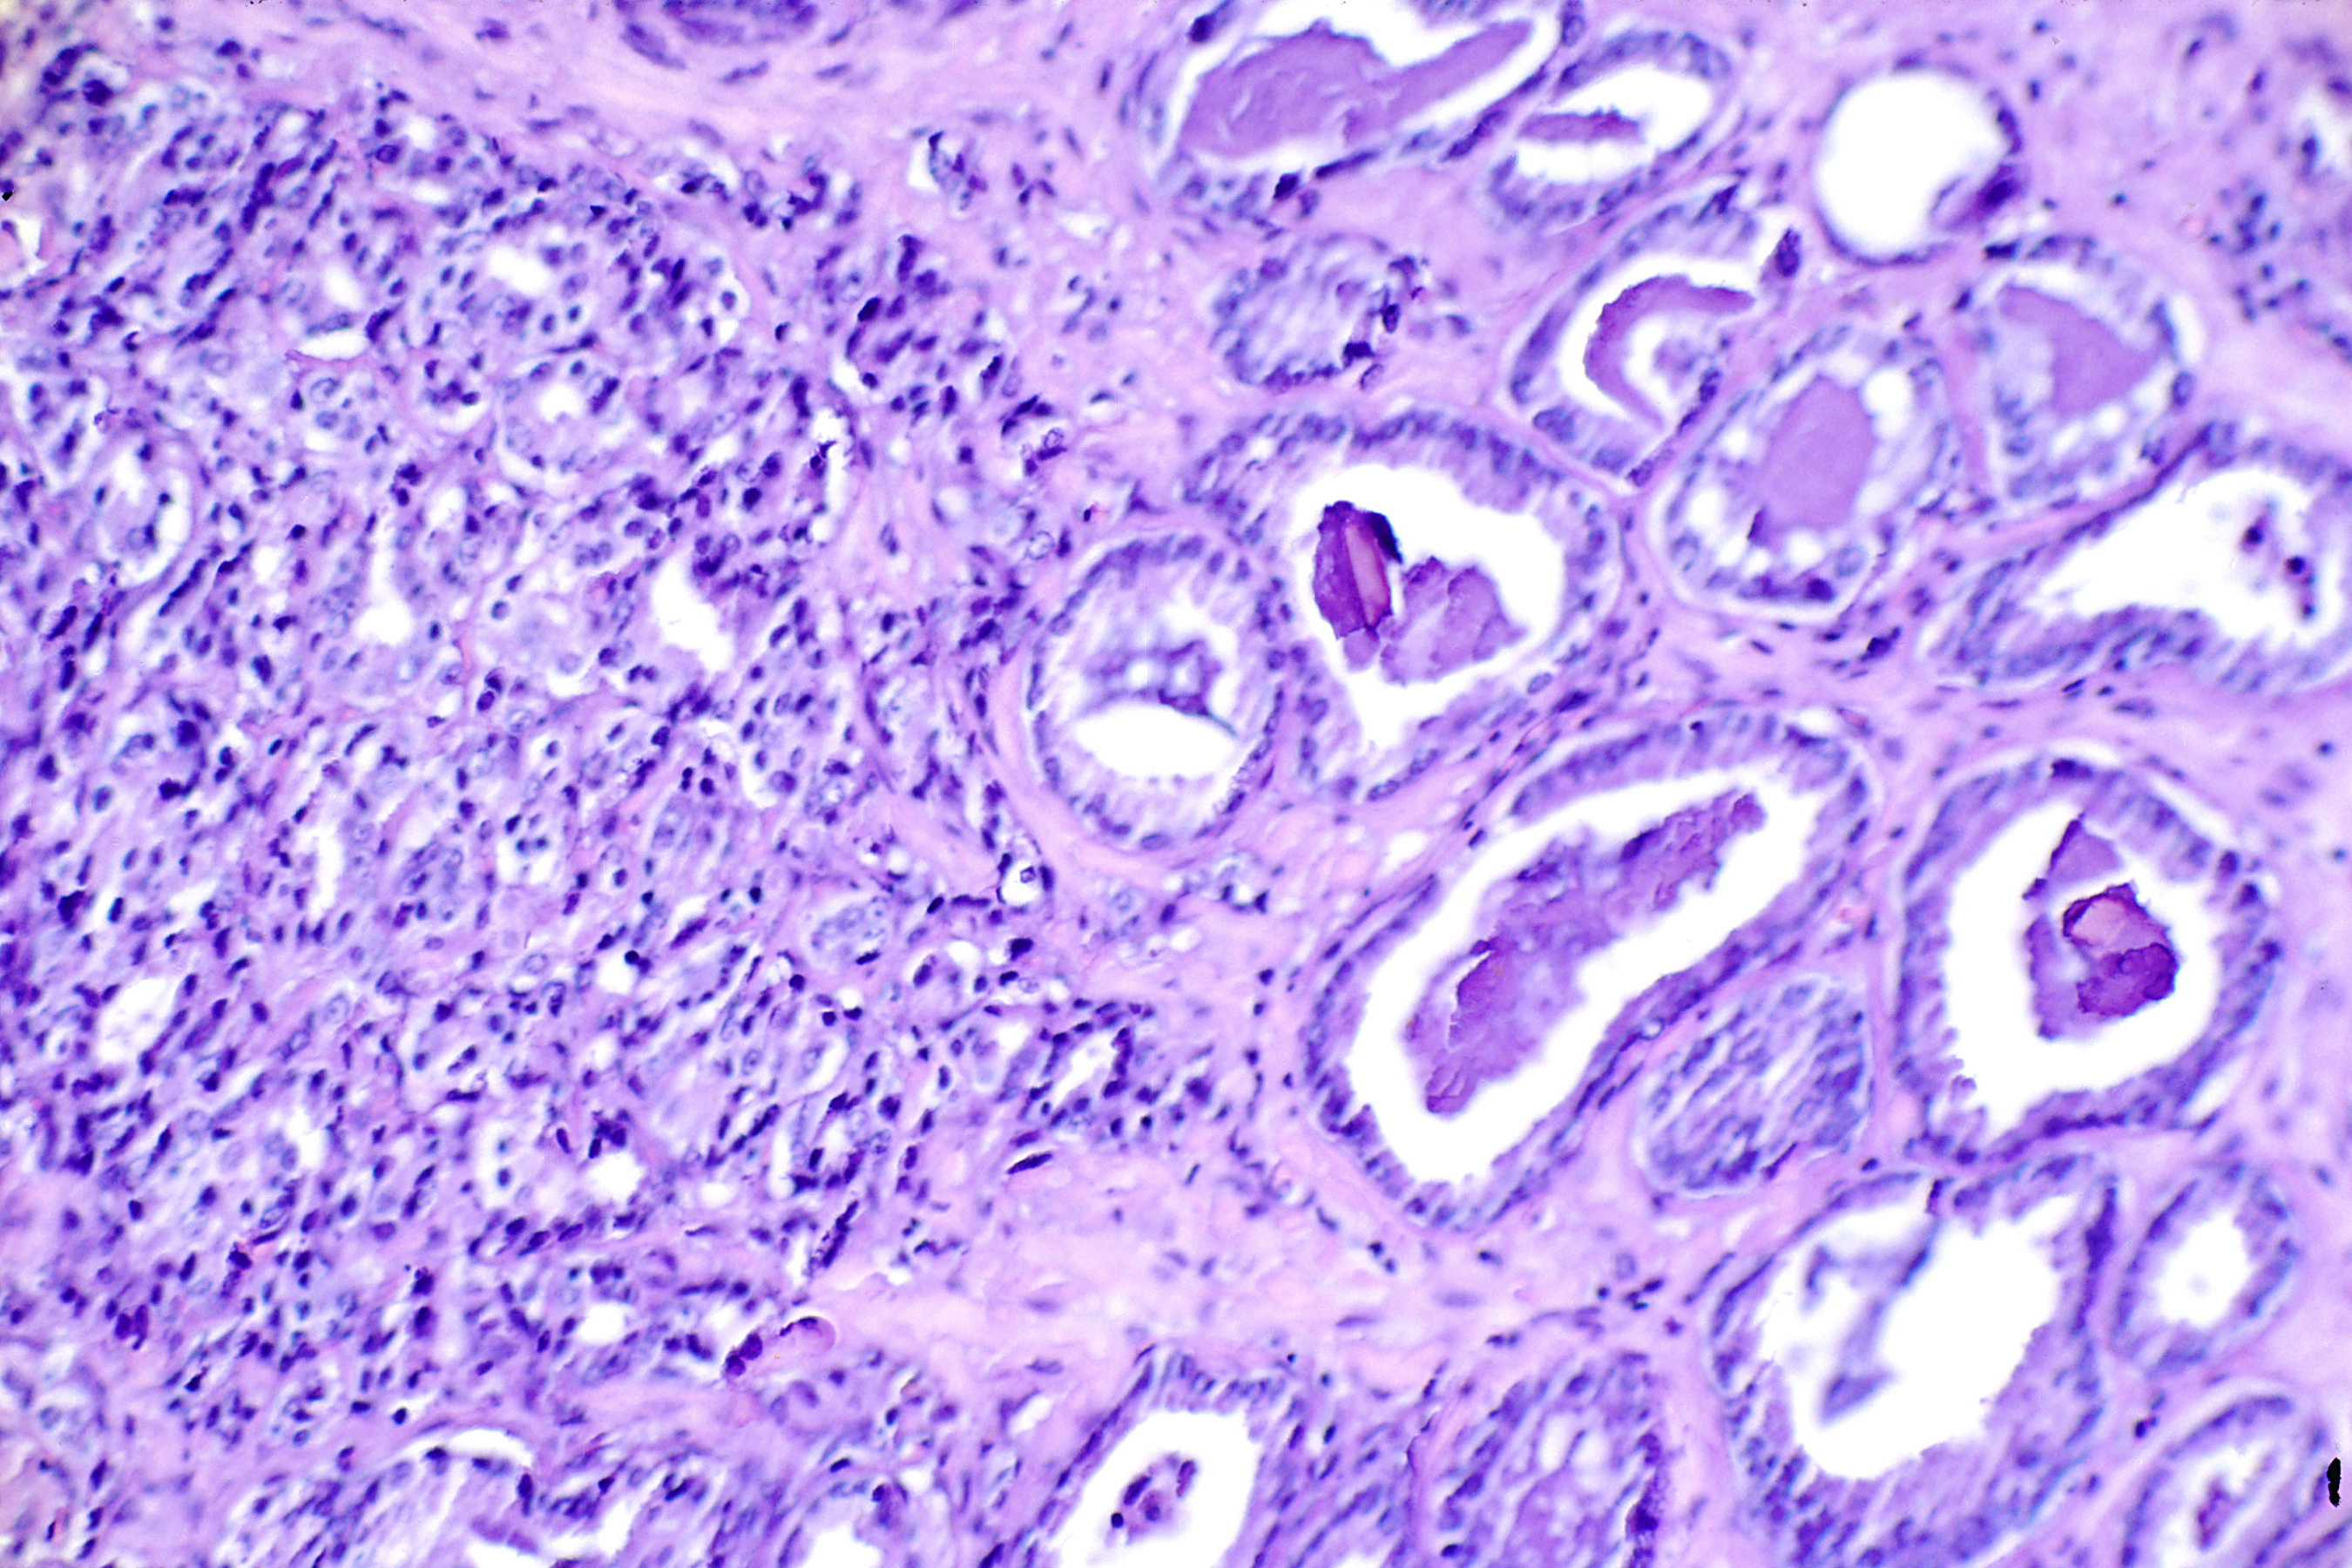

Эпителиально-мезенхимальная трансформация при РПЖ

Однако, несмотря на временный ответ на АДТ, у большинства пациентов развивается рецидивирование и резистентность к кастрации. Эпителиально-мезенхимальная трансформация (Epithelial-mesenchymal transition (EMT)) является комплексным процессом, в течение которого клетки теряют их эмбриональные характеристики и приобретают мезенхимальные особенности.

Все больше доказательств указывают на то, что ЕМТ способствует метастатическому прогрессированию рака предстательной железы и тесно коррелирует с повышенной лекарственной устойчивостью.